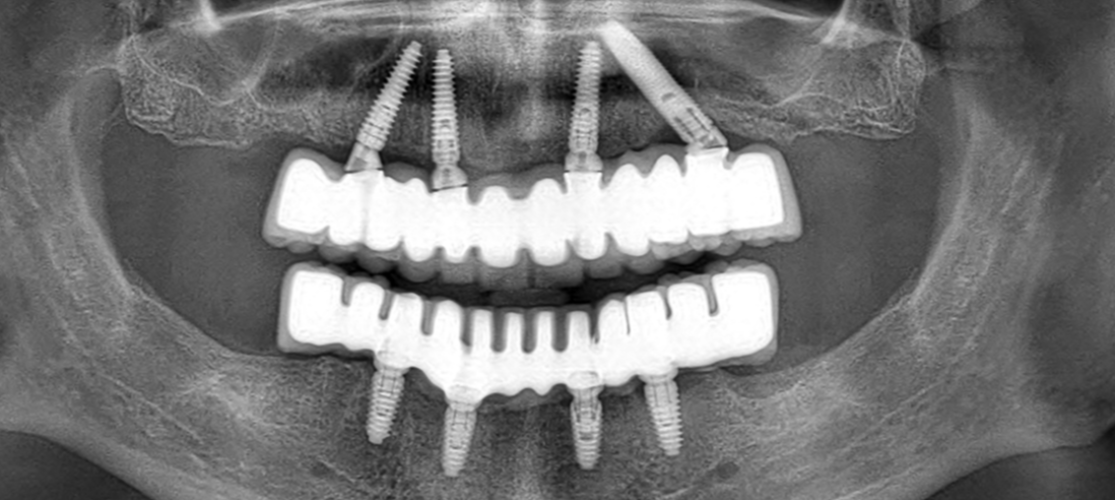

Die All on 4 Implantattechnik ist ein modernes und technologisches Verfahren, bei dem bei vollständig zahnlosen Patienten innerhalb eines Tages ein fester Zahnersatz auf vier eingesetzten Zahnimplantaten befestigt wird.

Im Unterschied zu den Standardimplantationstechniken eliminiert die All-on-4 Technik die klassische 3-6 monatige Heilungszeit, in der der Patient ohne Zahnersatz bleibt, indem die Implantate in unterschiedlichen Winkeln platziert und eine entsprechende Überbauung gewählt wird.

Nach der klinischen und radiologischen Untersuchung des Patienten wird die All-on-4 Implantattechnik mit Hilfe von Computertomographie geplant und sicher angewendet. Das All-on-4 Implantatsystem ist eine ideale Methode für Patienten mit Knochenschwund in den hinteren Zahnregionen, um feste Zähne zu verwenden.

Am Tag der Implantation oder am folgenden Tag wird dem Patienten ein fester provisorischer Zahnersatz eingesetzt, und die Implantate heilen mit diesen provisorischen Zähnen. Nach der Heilung werden die dauerhaften ästhetischen Zähne des Patienten eingesetzt.

Das All on 4 Verfahren umfasst die Platzierung von vier Zahnimplantaten in jedem Kiefer, um eine vollständige Zahnprothese zu stützen. Um den Kontakt mit dem Knochen zu maximieren, werden zwei Implantate vertikal im vorderen Bereich und zwei Implantate in einem Winkel im hinteren Bereich eingesetzt.